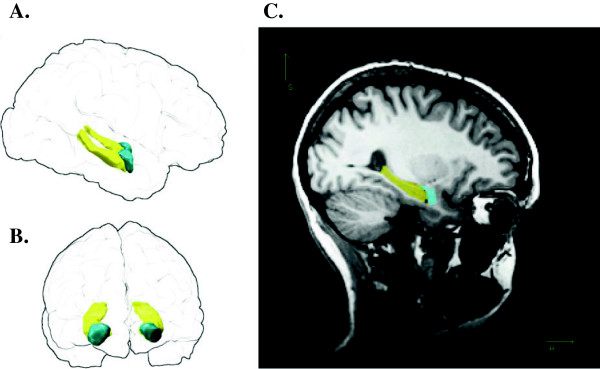

Background: Animal studies have suggested that the hippocampus may play an important role in anxiety as part of the Behavioural Inhibition System (BIS), which mediates reactivity to threat and punishment and can predict an individual's response to anxiety-relevant cues in a given environment. The aim of the present structural magnetic resonance imaging (MRI) study was to examine the relationship between individual differences in BIS and hippocampal structure, since this has not received sufficient attention in non-clinical populations. Thirty healthy right-handed participants with no history of alcohol or drug abuse, neurological or psychiatric disorders, or traumatic brain injury were recruited (16 male, 14 female, age 18 to 32 years). T1-weighted structural MRI scans were used to derive estimates of total intracranial volume, and hippocampal and amygdala gray matter volume using FreeSurfer. To relate brain structure to Gray's BIS, participants completed the Sensitivity to Punishment questionnaire. They also completed questionnaires assessing other measures potentially associated with hippocampal volume (Beck Depression Inventory, Negative Life Experience Survey), and two other measures of anxiety (Spielberger Trait Anxiety Inventory and the Beck Anxiety Inventory).

Results: We found that high scores on the Sensitivity to Punishment scale were positively associated with hippocampal volume, and that this phenomenon was lateralized to the right side. In other words, greater levels of behavioural inhibition (BIS) were positively associated with right hippocampal volume.

Conclusions: Our data suggest that hippocampal volume is related to the cognitive and affective dimensions of anxiety indexed by the Sensitivity to Punishment, and support the idea that morphological differences in the hippocampal formation may be associated with behavioural inhibition contributions to anxiety.